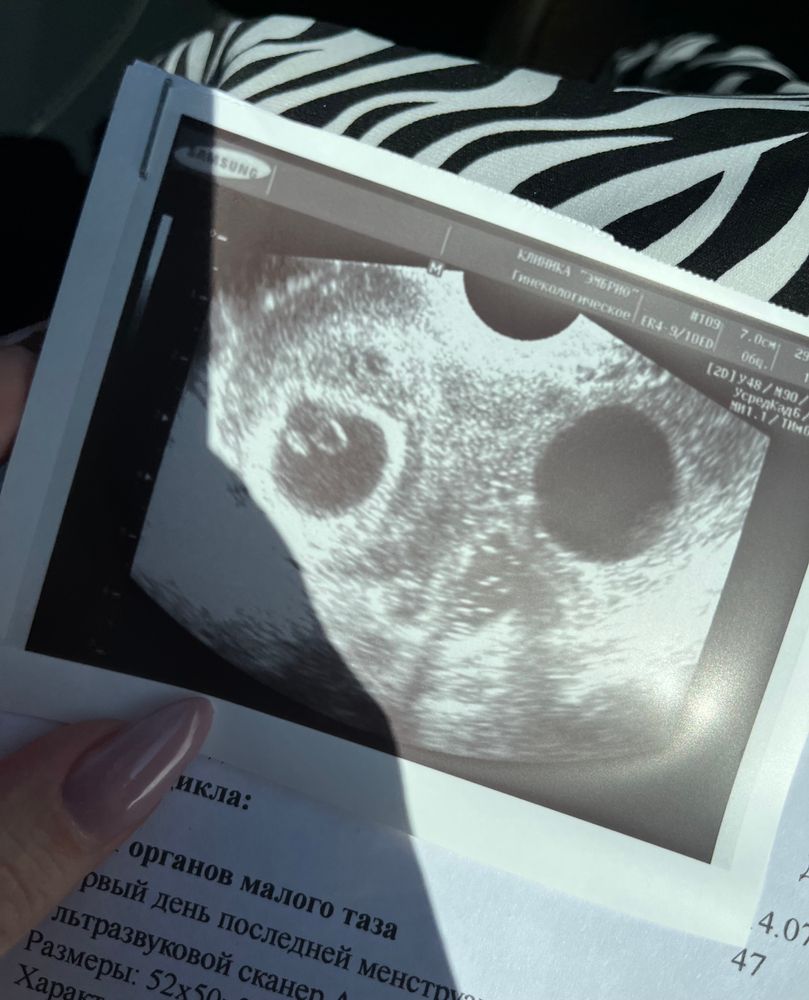

8й ДПП ХГЧ 98, 10й ДПП - 269, 13й - 1107. Подсаживали 2х пятидневок. Вроде как, тьфу-тьфу-тьфу, пока что все хорошо, один прикрепился, но мне вот интересно, могли ли второго проглядеть 🤔

У меня второе ПЯ появилось позже, через дня 3 после того как увидели первого, но к сожалению оказалось пустым, эмбрион был только в одном ПЯ

Анна, ого, второе то большое какое, либо ракурс такой.. По сути, конечно, главное чтобы и один был, главное, здоровый и всё с ним было бы хорошо 🙂

Анна Шанберова, да, ракурс такой, по факту оно было меньше первого, но не намного, по месячным одно шло в срок, а втрое отставало на 3-4 дня, и там не было ЖМ